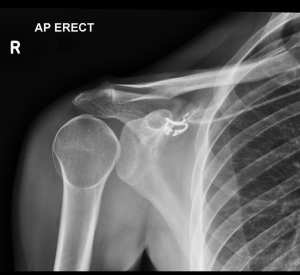

A 28-year-old man presents to the emergency department after a fall while riding his mountain bike. The patient states he went off a six-foot ramp and landed on his right shoulder. On physical exam, he is unable to move his right shoulder, and he holds the right upper extremity in internal rotation. An X-ray of the right shoulder is obtained, as seen above. Which of the following is the most likely diagnosis?

Answer: D

A posterior shoulder dislocation is caused by an axial force applied while the shoulder is internally rotated and abducted or by a direct blow to the anterior shoulder. With this injury, the arm will be held in adduction and internal rotation, and there is mechanical obstruction with active external rotation of the extremity. This injury is frequently missed because it is difficult to identify on radiographs. The subtle “light bulb” sign may be appreciated on the anteroposterior view of the radiograph. The axillary view is most helpful for diagnosis and will show the humeral head posterior to the glenoid fossa. Posterior shoulder dislocations are commonly associated with fractures of the surgical neck of the humerus, reverse Hill–Sachs deformities, and rotator cuff injuries. Procedural sedation should be given for reduction. The technique for reduction includes internal rotation and lateral traction to disimpact the humeral head from the glenoid rim, followed by external rotation. Reduction can be difficult, and orthopedic consultation for operative management may be required. The shoulder should be immobilized in external rotation with slight abduction.

Acromioclavicular separation (A) occurs most commonly from falling directly on the “point” of the shoulder, which causes the clavicle to separate from the scapula. Anterior shoulder dislocation (B) occurs with force on the extremity while in abduction, external rotation, and extension. This is the most common type of shoulder dislocation. The radiograph will show the humeral head anterior, medial, and inferior to the normal location. A clavicle fracture (C) usually occurs from falling onto the lateral shoulder, onto an outstretched arm, or from a direct blow. The majority of fractures occur in the middle third of the clavicle.